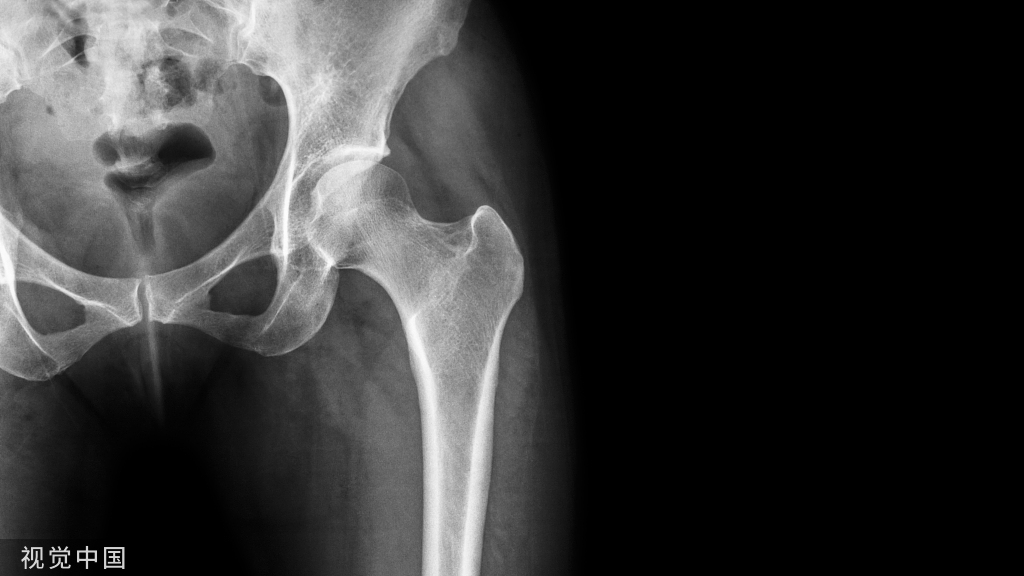

图 1  下胫腓联合螺钉示意图

由左向右分别为完整、松动、断裂、取除后的下胫腓联合螺钉(图片来自文献 [1])

那么,究竟有无必要取除下胫腓联合螺钉以使患者获得理想的功能恢复呢?最近荷兰阿姆斯特丹医学科研中心创伤外科的 Dingemans 等 [2] 在 Bone Joint Journal 上发表了一篇系统综述,他们得出结论:不应常规取除下胫腓联合螺钉。

Dingemans 通过 Medline、Embase 和 Cochrane Library 等权威数据库检索所有关于下胫腓联合螺钉的文献,最终取除和保留下胫腓联合螺钉的 11 篇文献纳入研究。

虽然入选的 11 项研究都存在一些方法上的缺陷,但是所得的研究结论却比较一致。2 项随机对照试验研究均发现,移除与保留下胫腓联合螺钉的患者功能预后无明显区别。9 项病例对照研究中的 8 项证明保留下胫腓联合螺钉可获得相同或者更好的功能预后。因此,Dingemans 等认为在缺少高质量证据的情况下,不应常规取除下胫腓联合螺钉